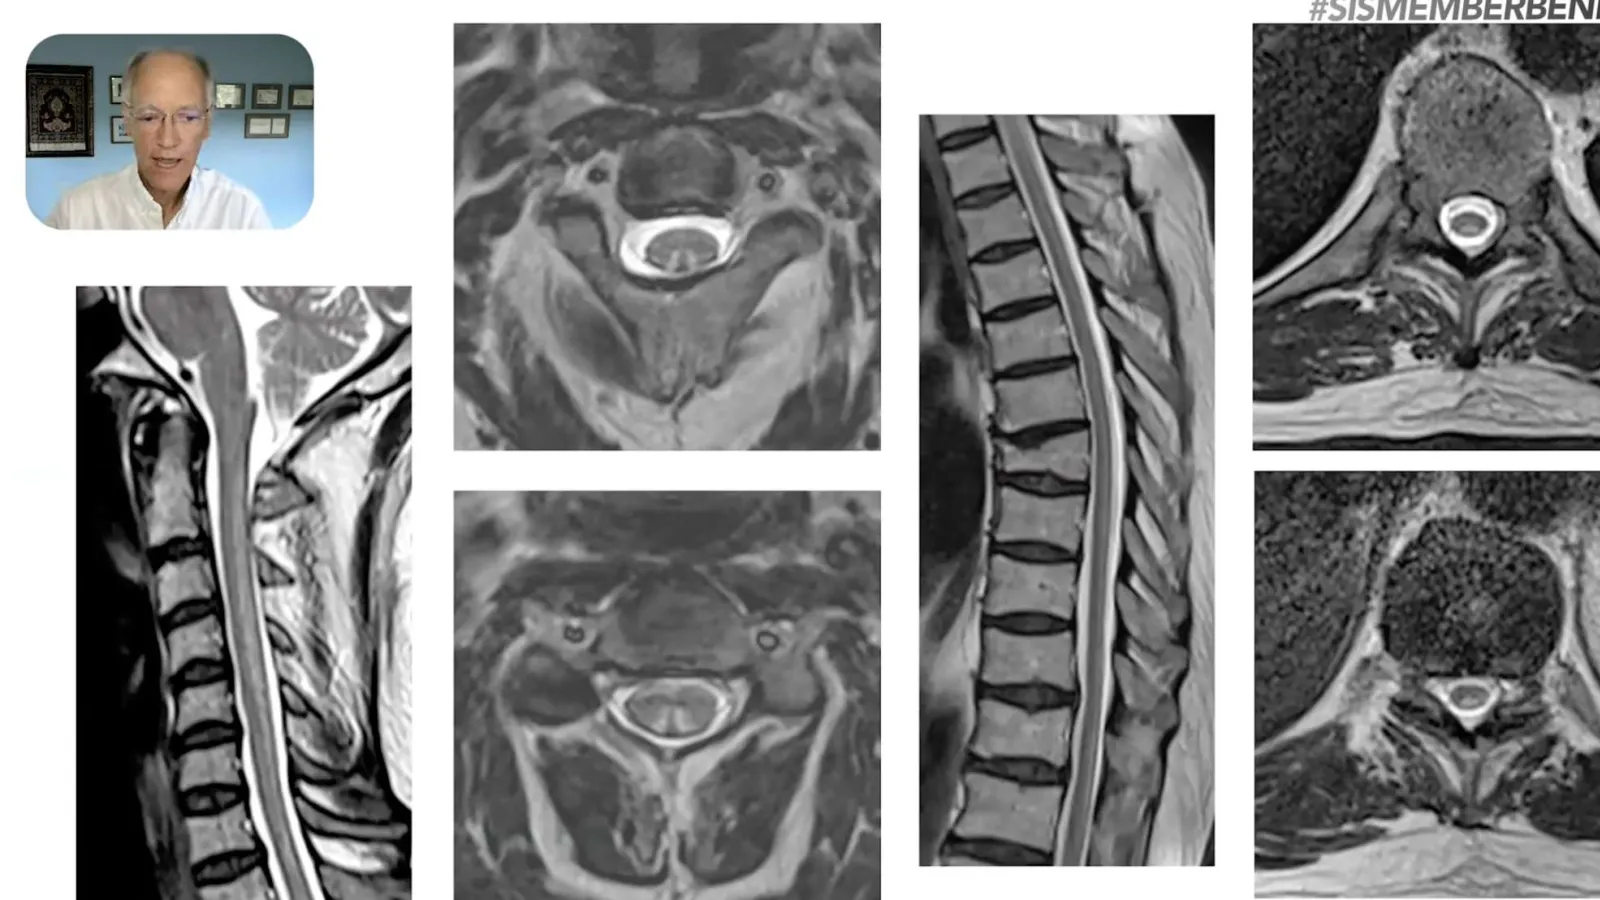

Composite image of spinal MRI scans highlighting vertebrae and discs alongside a doctor explaining findings in a video.

Case Review Community feat. Dr. Rajeev Valvani (Part 1)

Comparison of spinal cord MRI scans showing pre-treatment and post-treatment improvements in degeneration.

Case Review Community feat. Dr. Rajeev Valvani (Part 2)